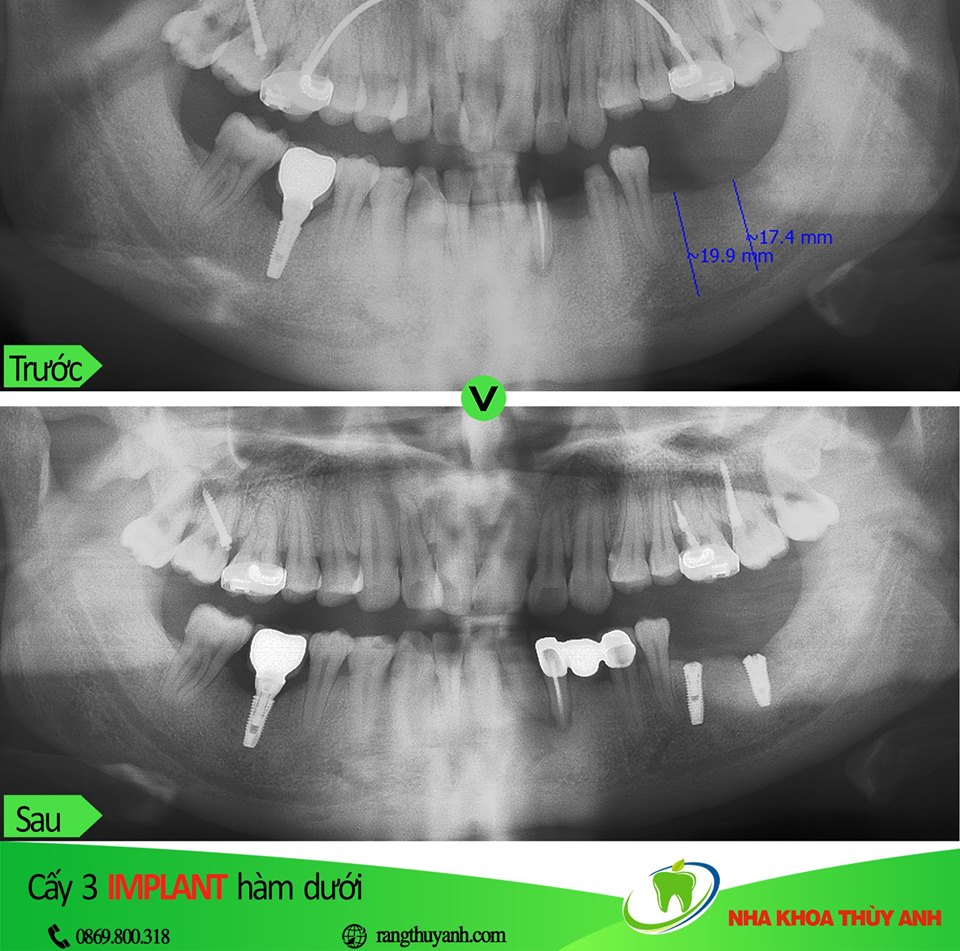

Trong bài viết hôm nay chúng tôi cung cấp thong tin về chủ đề ghép xương, nâng xoang trong cấy ghép implant. Đây là chủ đề không dễ để hình dung. Có thể nói là 1 nhánh nhỏ hỗ trợ cho việc cấy ghép implant nên kiến thức rất sâu. Không phải ca cấy implant nào cũng cần ghép xương, chỉ trong một số tình huống đặc biệt hoặc yêu cầu cao về thẩm mỹ chúng ta mới cần thực hiện.

Ghép xương –nâng xoang là 1 nhánh nhỏ hỗ trợ cho việc cấy ghép implant nên kiến thức rất sâu. Không phải ca cấy implant nào cũng cần ghép xương, chỉ trong một số tình huống đặc biệt hoặc yêu cầu cao về thẩm mỹ chúng ta mới thực hiện.

Ghép xương là một thuật ngữ thường được nhắc đến khi thực hiện trồng implant, ghép xương được bác sĩ chỉ định khi vị trí trồng răng có mật độ xương hàm không đạt tiêu chuẩn để đặt trụ implant. Cùng tìm hiểu cụ thể hơn về ghép xương khi trồng răng trong bài viết dưới đây.